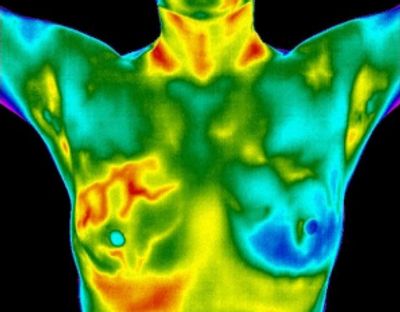

Thermography is a radiation-free, state-of-the-art screening procedure that uses heat detection to locate areas of temperature differences in the body. Most pathological processes demonstrate a form of increased heat, and some neurological processes show excessive cold, or hypothermia Breast disease can be detected by looking for areas of excessive or increasing heat that may indicate areas of angiogenesis, or increase of blood vessels supplied by a growing tumor.

Breast Thermography is a non-invasive and painless way to screen for breast cancer without radiation or compression of the breast. It uses state of the art medical infrared technology to assess heat in the breast. Comparative exams create a baseline for monitoring breast health based on individual thermal patterns and changes.

In the realm of breast thermography, the focus is on identifying heat patterns in the breast that could be indicative of pathology. Tumor growth typically results in increased vascular patterns, which can be detected using advanced infrared cameras. Thermography aims to establish a baseline for overall breast health and wellness.